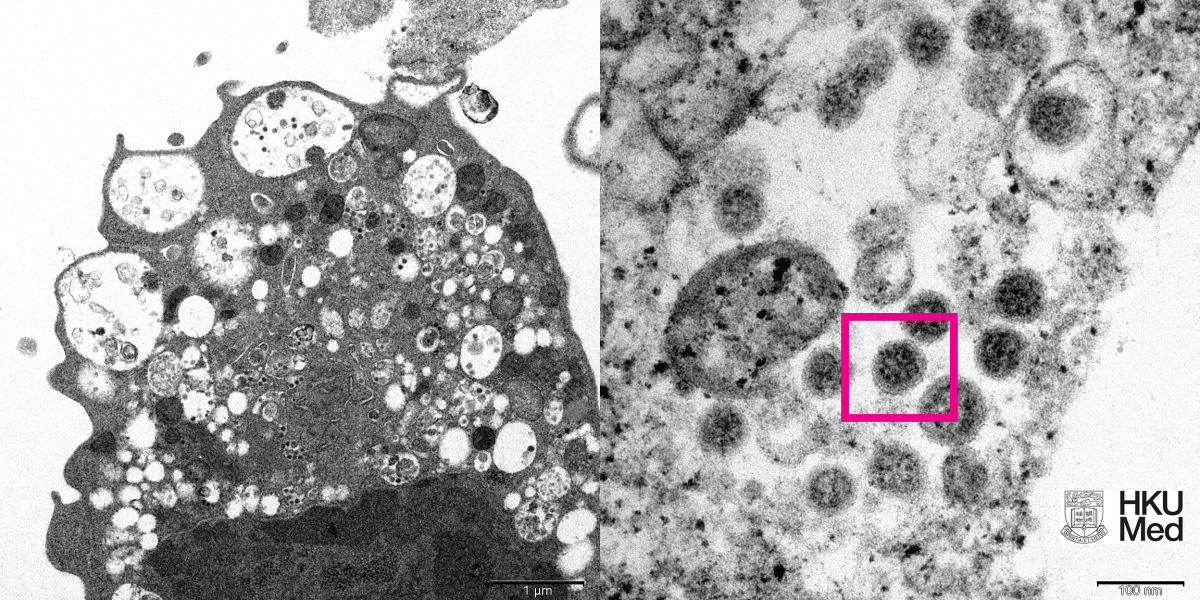

Изображения в двух вариантах — с малым и большим увеличением. Первое (слева) показывает повреждение клеток с набухшими везикулами, содержащими маленькие чёрные вирусные частицы. Второе (справа) демонстрирует агрегаты вирусных частиц с шипами в форме короны на их поверхности.